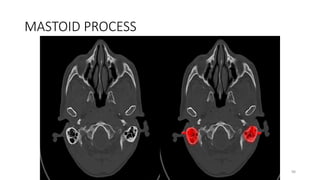

MASTOID PROCESS